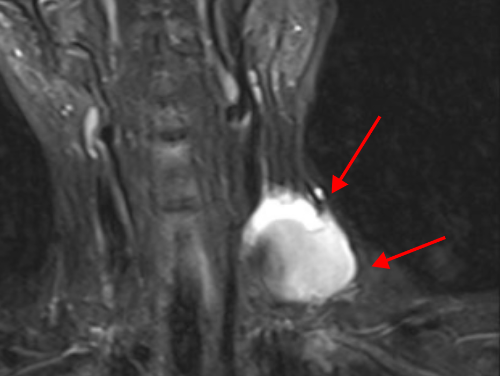

冯医生表示,文女士的静脉瘤体巨大,最大直径有7cm,一旦破裂会有生命危险;同时,静脉瘤体中有大量血栓,瘤体破口长度约2cm,存在血栓脱落导致肺栓塞的风险;静脉瘤病史时间较长,局部有血栓性静脉炎表现,内部组织粘黏情况较重,如何精准剥离黏连组织,切除肿块的同时重建颈部静脉是手术的关键,同时注意避免损伤胸导管,造成难治性淋巴漏。

手术过程中,冯医生首先游离左颈内静脉远端正常段并悬吊带悬吊备用,直视下穿刺左颈内静脉并引入6F短鞘,导入10mm球囊对左颈内静脉近心端进行球囊阻断。在病变血管近、远端同时阻断条件下,对颈内静脉瘤进行解剖,打开瘤腔,找到破口后予以缝合,同时清除瘤腔内血栓。